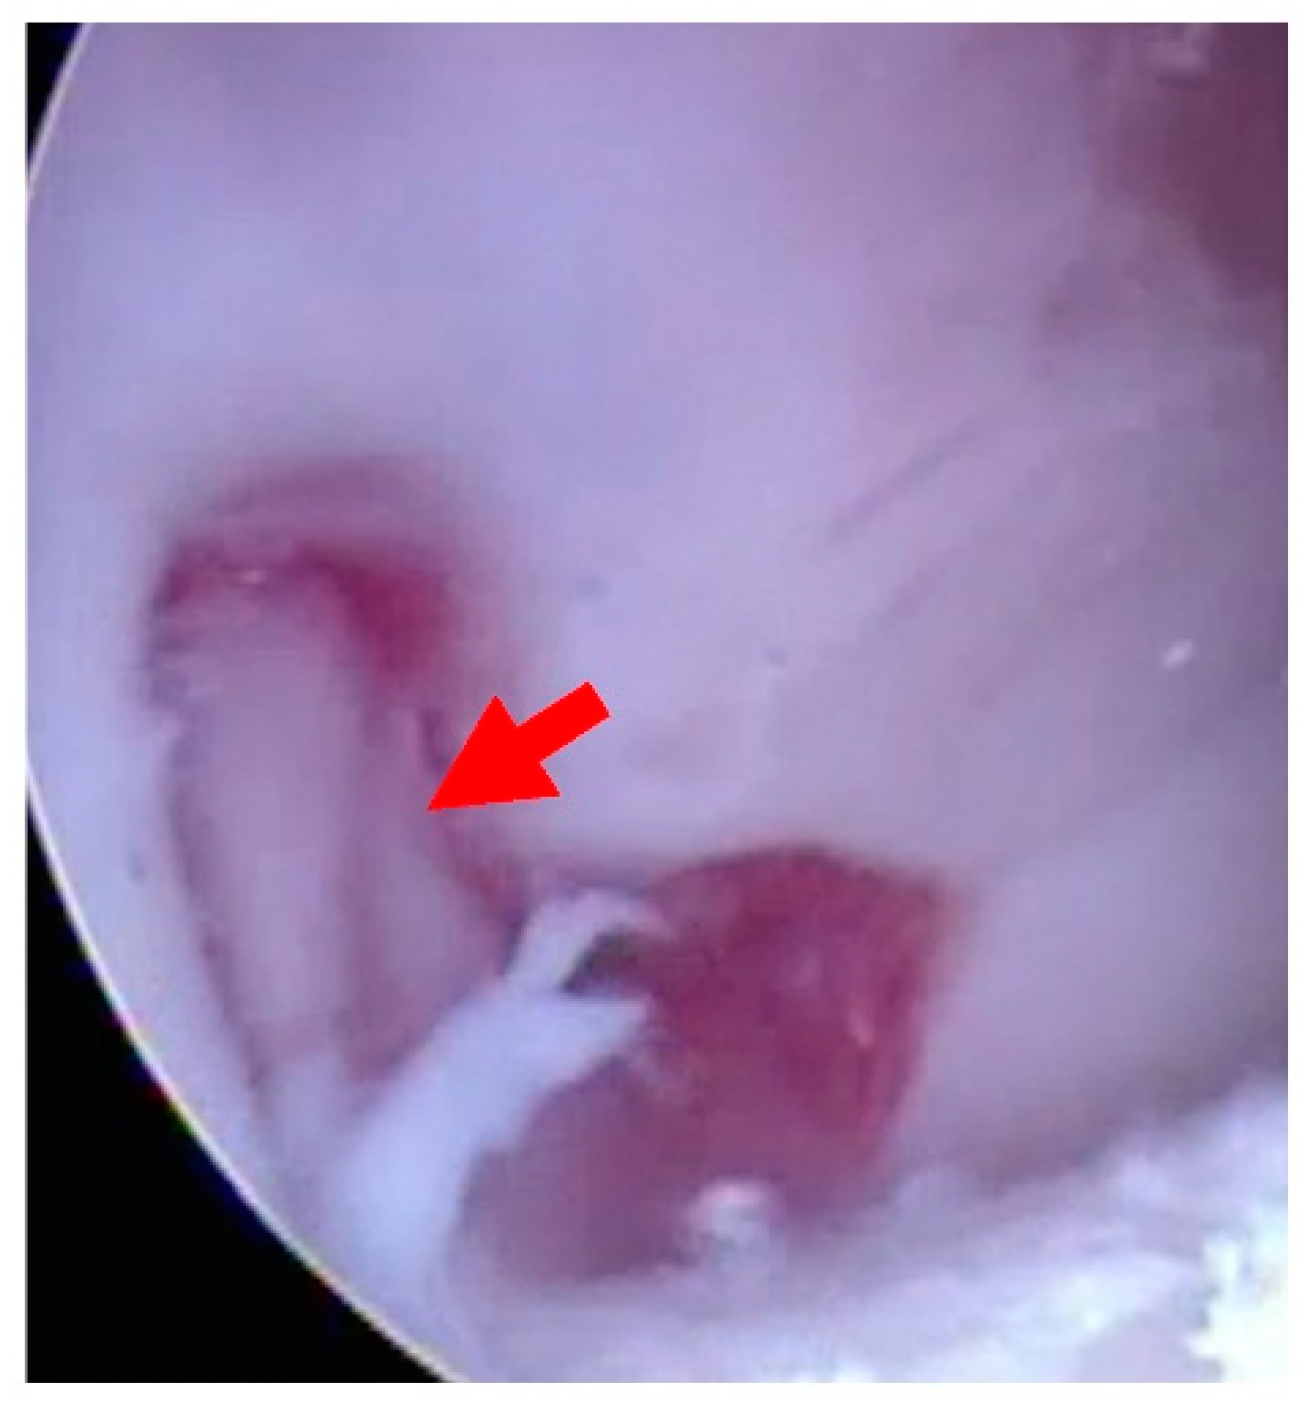

- Softening of the articular surface (Figure 2)